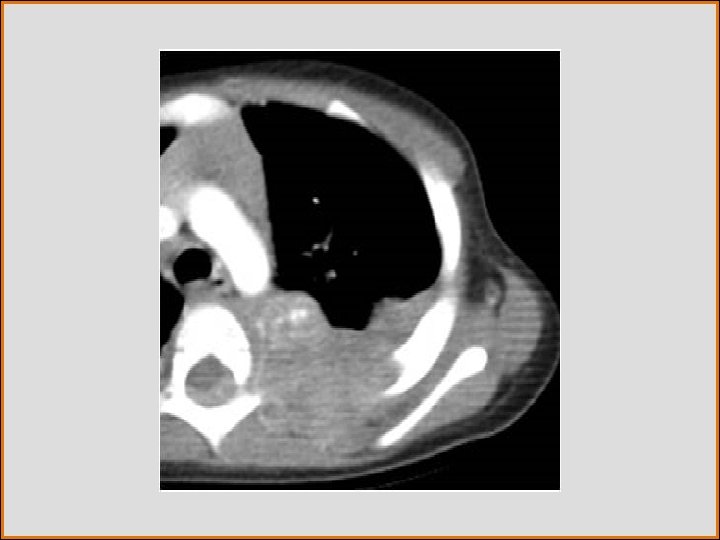

Case History • A CT was performed

Test Your Diagnosis What is the most likely diagnosis? a. Chondrosarcoma b. Thoracic neuroblastoma c. Bronchogenic cyst d. Paraspinal abscess e. Thoracic aortic aneurysm

FINDINGS • CT confirms the posterior mediastinal mass with areas of calcification